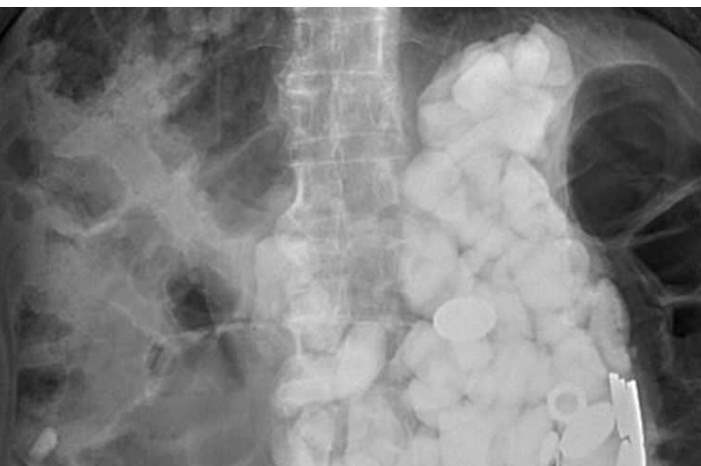

تفاجئ أطباء بعدما عثروا على مجموعة من الحجارة وأغطية زجاجات ونقود معدنية في معدة مريض، أجروا له عملية جراحية لإخراجها بعد أن تناولها أثناء تعرضه لنوبات قلق.

وأجرى أطباء بمستشفى Ilsan Paik بجامعة إنجي الكورية الجنوبية، مجموعة من الفحوصات لمعرفة السبب الكامن وراء هذه الأعراض، حيث شعروا بشيء يشبه الحجارة عند لمس بطنه، واكتشفوا تراكم أجسام في المعدة كلها يصل وزنها إلى كيلوغرامين.

ولم تفلح محاولات الأطباء في إخراج الأجسام من معدة الرجل الذي ولد بإعاقة ذهنية، باستخدام طريقة المنظار نظرا لكثرتها، مما دفعهم للحل الجراحي.